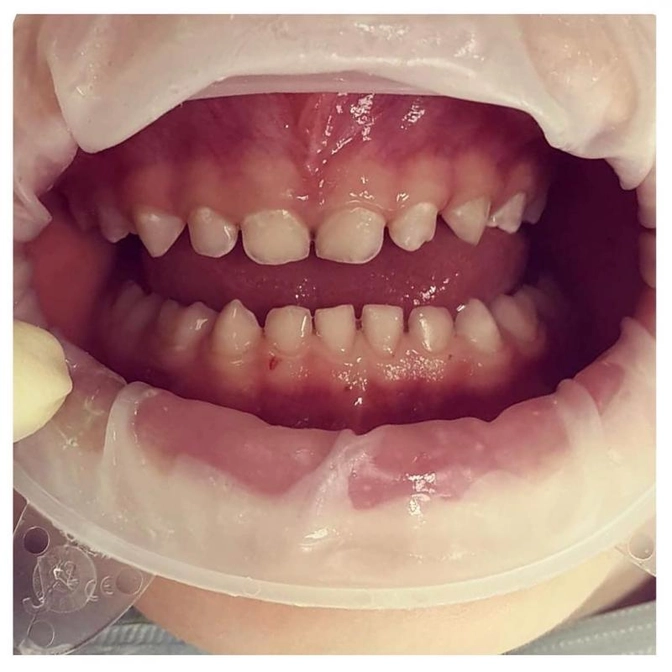

Пациентка детского стоматолога Полины Акиншиной.

Ребенку 5 лет.

Проведена профессиональная гигиена.

А под налетом обнаружены вот такие белые пятна.

Что это, есть варианты?

Это самый настоящий кариес.

Кариес в стадии пятна.

Обратите внимание на центральные зубы верхней и нижней челюсти.

Есть такое понятие - центральная линия.

Это воображаемая линия, проходящая чётко по центру между центральными зубами.

В норме она плавно «перетекает» с верхней челюсти на нижнюю.

А теперь попробуйте мысленно провести ее здесь.

У вас получится не прямая линия, а изогнутая.

Потому как нижняя челюсть смещена влево относительно верхней.

Это явление так и зовётся - смещение центральной линии.

Так формируется неправильный прикус, называется перекрестный.